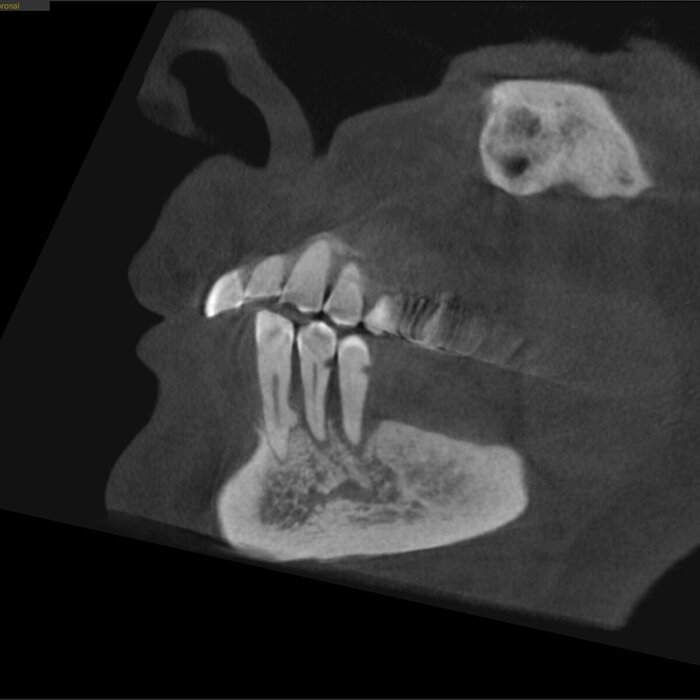

Отправила снимок КЛКТ, дождалась ответа и плана лечения, в январе проводила мужа в СПб из своего города (северного) сразу же на операционный "стол".

Синус лифтинг:

Всё хорошо, но есть ещё правая сторона, которая посложнее.

КЛКТ

Да и смысл добавлять скан - всё видно и понятно. На нижней челюсти 4 зуба, которые никуда не годятся.

Справа - одинокий воин.

Слева - компания друзей навынос.

Белые точки на нижней челюсти - маячки.

Сделали КЛКТ:

Что бы точно никаких вопросов не осталось у доктора, сделали ОПТГ:

ОПТГ